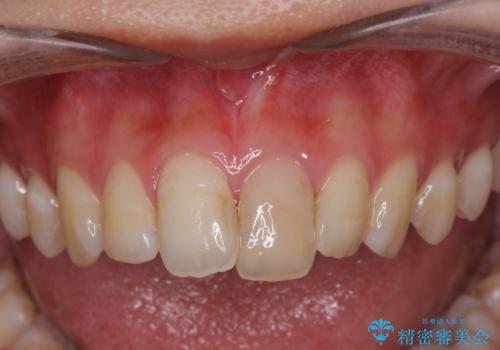

- 以前に前歯を強打し、変色してきた前歯の審美性の改善を希望されて来院されました。

歯科技工士との綿密な打ち合わせで、非常に自然なセラミッククラウンを作製することができました。